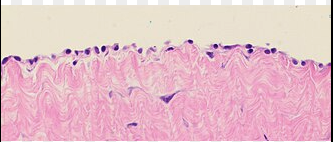

Mesotel

• Enkelt skivepitel som bekläder serösa hålrum (pleura, peritoneum, perikard).

• Friktionsminskning, barriär.